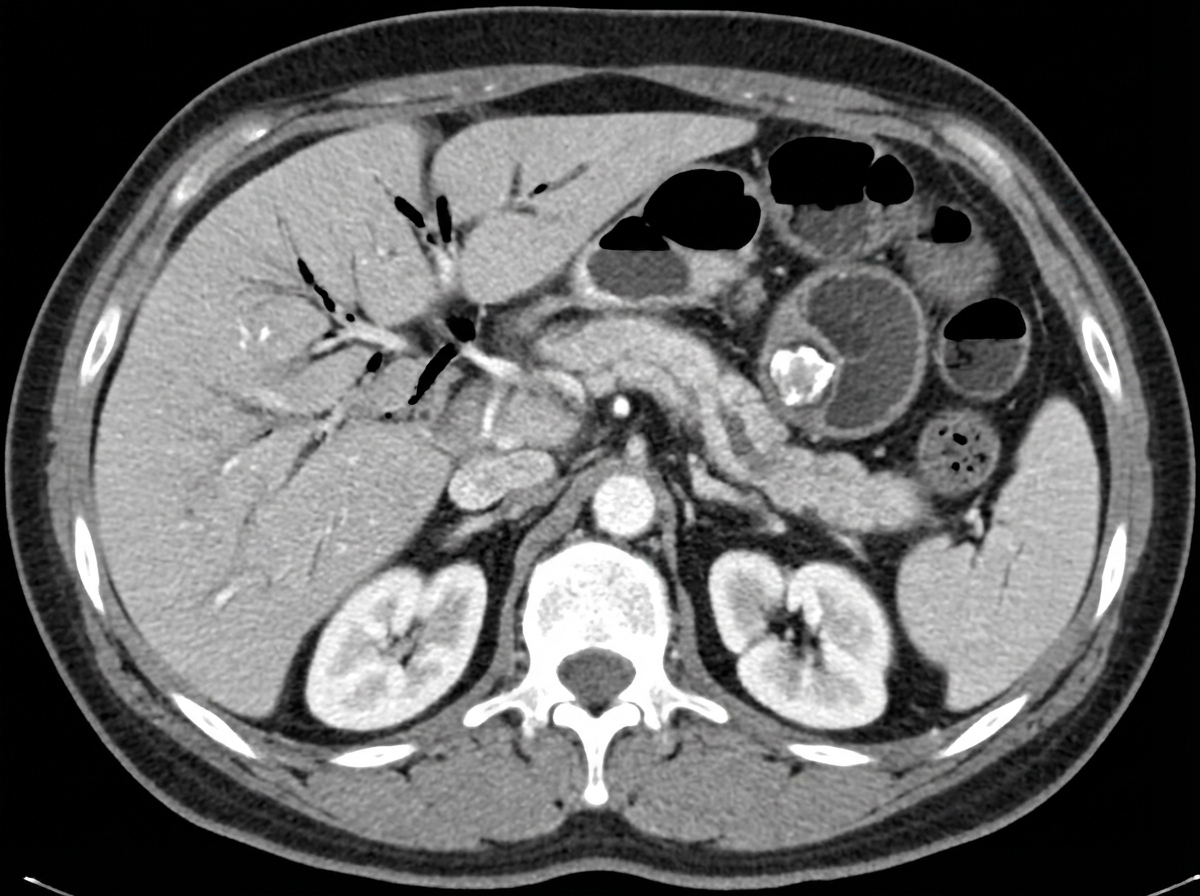

A 79-year-old man presents to the emergency department with abdominal pain. The patient describes the pain as severe, tearing, and radiating to the back. His history is significant for hypertension, hyperlipidemia, intermittent claudication, and a 60 pack-year history of smoking. He also has a previously diagnosed stable abdominal aortic aneurysm followed by ultrasound screening. On exam, the patient's temperature is 98°F (36.7°C), pulse is 113/min, blood pressure is 84/46 mmHg, respirations are 24/min, and oxygen saturation is 99% on room air. The patient is pale and diaphoretic, and becomes confused as you examine him. Which of the following is most appropriate in the evaluation and treatment of this patient?

A 68-year-old woman comes to the emergency department because of abdominal pain for 3 days. Physical examination shows guarding and tenderness to palpation over the left lower abdomen. Test of the stool for occult blood is positive. A CT scan of the abdomen is shown. Which of the following mechanisms best explains the patient's imaging findings?